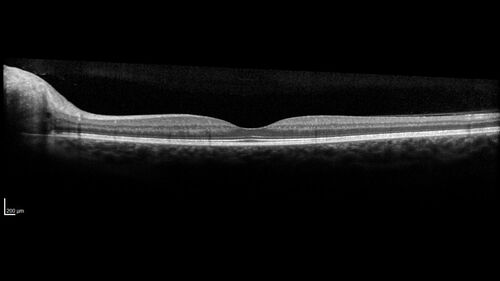

Advanced age-related macular degeneration

87 year old female. Severe macular bleed 15 years ago OD. Now with disciform scar. Left eye has progressing geographic atrophy.

VA OD: HM, OS: 5/200. IOP normal OU